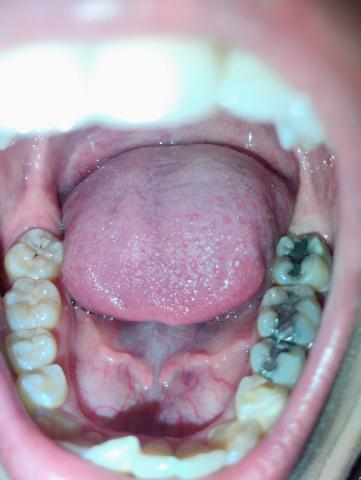

The image shows the lower dental arch with visible metallic (amalgam) restorations on posterior molars. There are signs of plaque accumulation and dark staining within the grooves of treated teeth.

Multiple amalgam (silver) fillings on lower molars

Dark discoloration around restoration margins

Plaque accumulation along occlusal grooves

Mild staining on adjacent teeth

Gum tissue appears generally stable

No obvious acute swelling visible

Tongue positioned normally